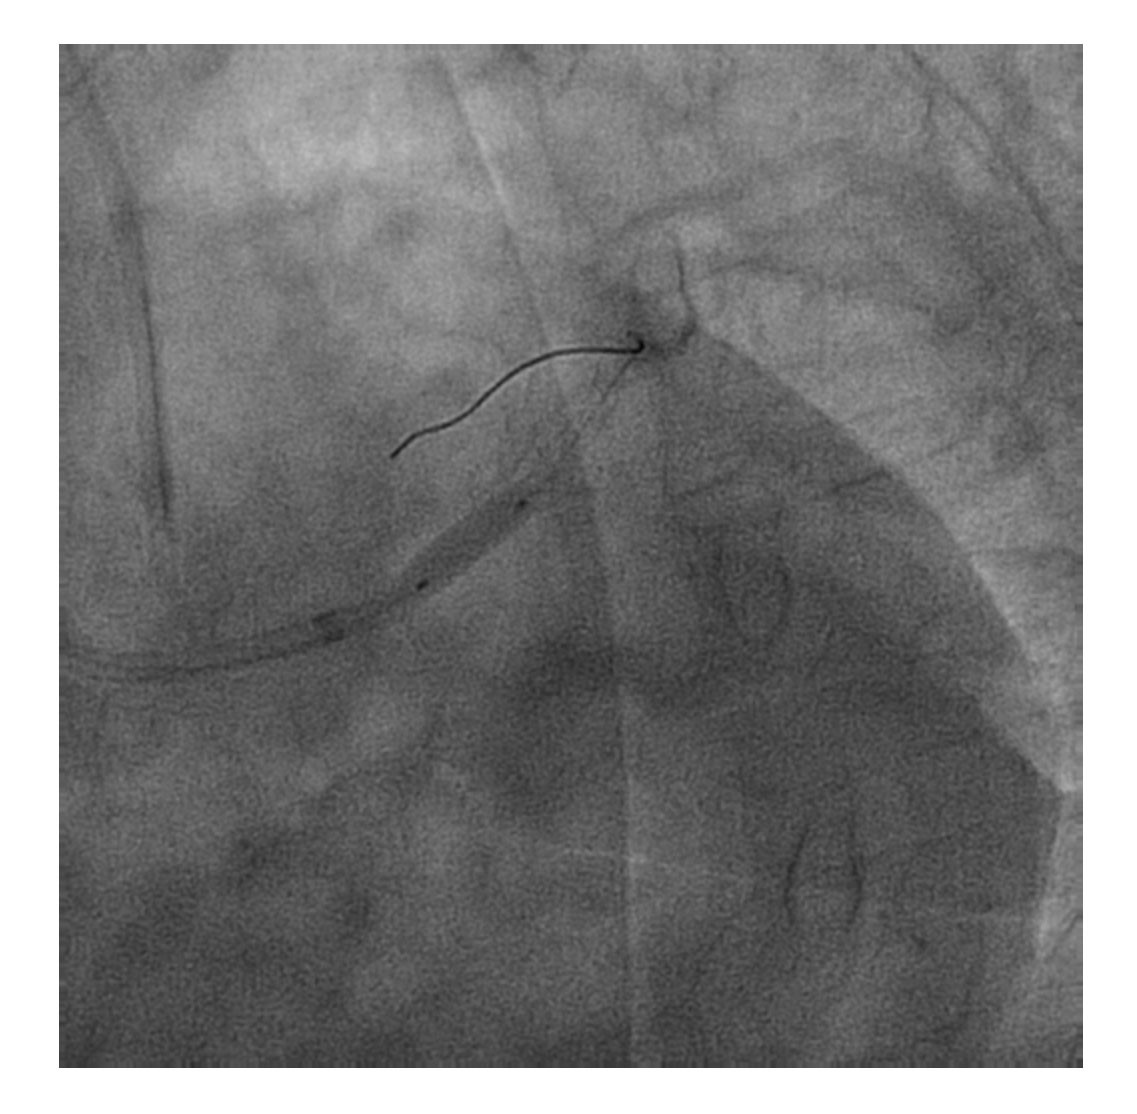

El procedimiento se efectuó bajo anestesia general, mediante abordaje femoral bilateral. Se colocaron 2 catéteres guía Extra Back Up (EBU) de 3,5 mm, de 6 y 7 Fr, en el tronco común izquierdo (técnica ping-pong). Se realizó predilatación secuencial de los ostia coronarios de la descendente anterior y las ramas intermedias mediante un balón de corte de 2,0 mm (vídeo 1 del material adicional) y se implantaron simultáneamente 3 stents farmacoactivos en la descendente anterior (stent liberador de sirolimus, de 2,25 × 15 mm), la primera rama intermedia (stent liberador de zotarolimus, de 2,25 × 18 mm) y la segunda rama intermedia (stent liberador de sirolimus, de 2,25 × 18 mm), por este orden; posteriormente se realizó un inflado simultáneo (figura 2). Por disección retrógrada se implantó un cuarto stent farmacoactivo (stent liberador de zotarolimus, de 4 × 8 mm) en el tronco común izquierdo (figura 3 y vídeo 2 del material adicional), con buen resultado por tomografía de coherencia óptica (figura 4A, B). Inmediatamente después de la intervención coronaria percutánea (ICP) se implantó una válvula aórtica expandible con balón de 23 mm (figura 5 y vídeo 3 del material adicional), también con buen resultado (figura 6 y vídeo 4 del material adicional).

Figura 3. Implante de un stent farmacoactivo en el tronco común izquierdo.